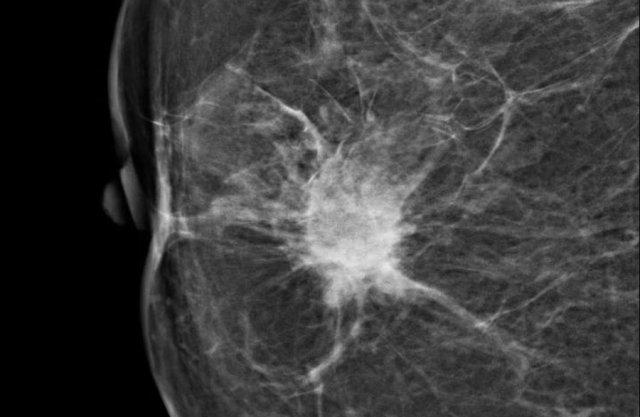

Đây là hình ảnh một khối tăng tỷ trọng với hình dạng không đều và bờ tua gai.

Lưu ý hiện tượng co rút da khu trú.

Trường hợp này được phân loại BI-RADS 5 và được xác nhận là ung thư biểu mô tuyến vú xâm lấn.